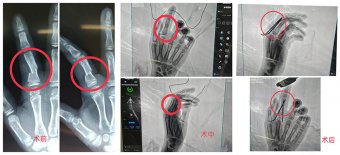

【案例分享】小孩手指砸傷骨折!我院創(chuàng)傷外科順利實(shí)施骨折復(fù)位手術(shù) 日期:2021-03-13 09:06:17 點(diǎn)擊:2215 好評:46

近日,濰坊市市立醫(yī)院創(chuàng)傷外科為一位11歲小朋友實(shí)施了右手示指近節(jié)指骨閉合復(fù)位克氏針內(nèi)固定術(shù)及石膏外固定術(shù),幫助小患者手指骨折部位成功復(fù)位。 骨折部位手術(shù)前后對比 小朋友在家中被歪倒的書架砸傷了右...